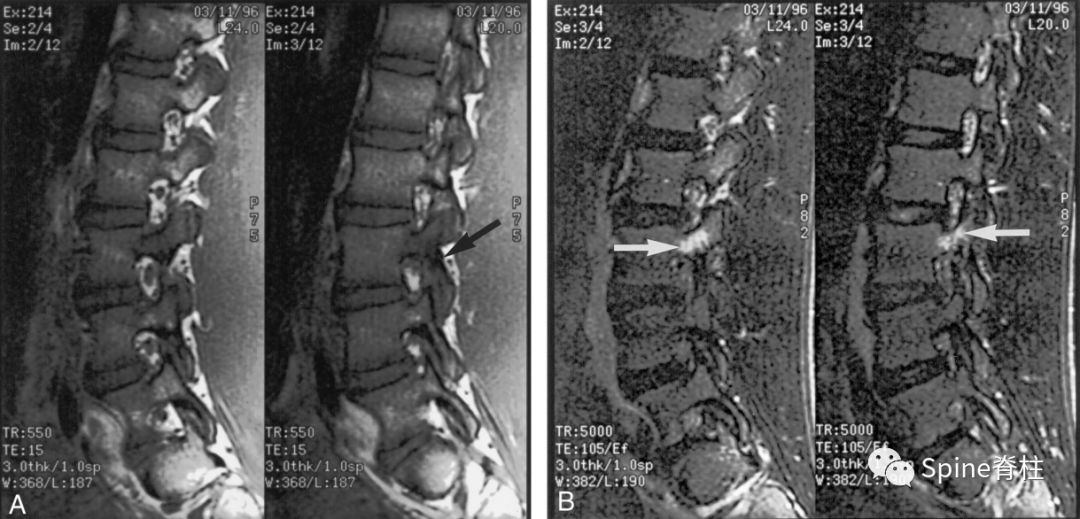

16岁的足球运动员诉右腰部疼痛。A:右侧T1加权像可见腰5峡部和椎弓根呈低信号(箭头);B:右侧T2加权像可见腰5峡部、椎弓根和关节突呈高信号(箭头)。

17岁的篮球运动员诉腰痛。A:T1像,左侧腰3峡部呈不连续的低信号(箭头);B:T2像,左侧腰3椎弓根和峡部呈高信号(箭头)

16岁的足球运动员,诉腰痛,以左侧为重。A:T1像可见腰5左侧峡部完全断裂(箭头);B:T2像,腰5左侧峡部、椎弓根和关节突水肿信号(箭头)

13岁运动员,左侧腰骶部疼痛。A:T1像,左侧腰5峡部完全断裂(箭头);B:T2像,左侧腰5峡部清晰可见,骨质无信号改变,峡部缺损处可见轻微的高信号,提示可能为肉芽组织或积液